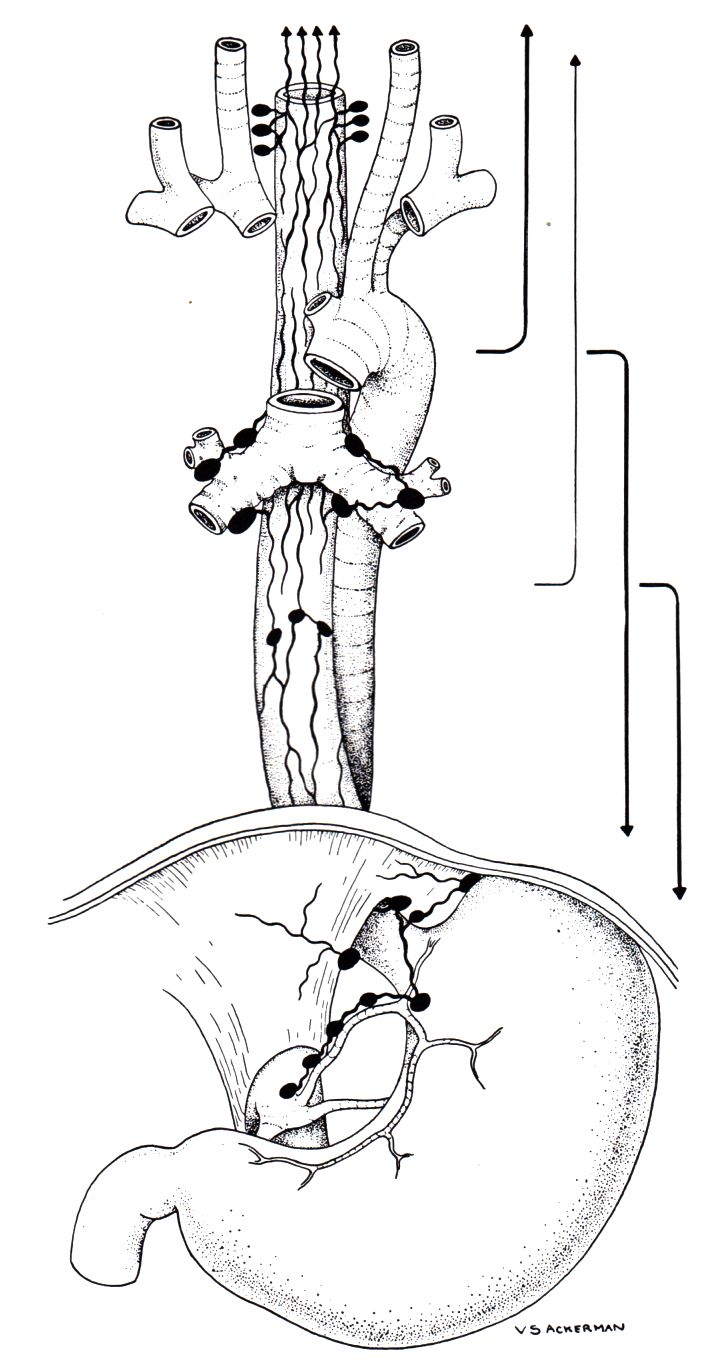

Lymphabfluss des Ösophagus

Lymphabfluss

Lokale Ausbreitung im Mediastinum, Lymphnoten-Metastasen in der CC-Achse, Lungen- und Lebermetastasen.